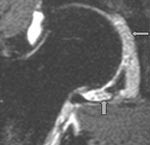

Degenerativ labrum viste økt signalintensitet i labrum uten affeksjon av overflaten med inntakt recess hos to pasienter (fig 3) og med manglende fremstilling av recess hos tre pasienter (fig 4). Sistnevnte ansees forårsaket av labrumhypertrofi. Labrumruptur ble diagnosisert hos ti pasienter. Ruptur ble beskrevet når man kunne identifisere kontrast mellom labrum og acetabulum (fig 5) eller imbibering av kontrast i labrum (fig 6). Alle rupturene satt i øvre del av labrum.To av disse pasientene er operert, og vårt funn ble verifisert. Begge var aktive fotballspillere, og de hadde henholdvis stadium 2B og stadium 3B ved MR-artrografi. Dette samsvarte med de artroskopiske funn. Den tredje pasienten som er operert, viste forandringer forenlig med villonodulær synovitt. Også dette ble verifisert ved artroskopi (fig 7).

Vi brukte Czerny og medarbeideres klassifikasjon av labrumskader ved MR-artrografi (2). Stadium 0 er normal labrum. Stadium 1 viser økt intralabral signalintensitet, forenlig med degenerativ labrum. Stadium 2 viser imbibering av kontrast inn i labrum, forenlig med ruptur. Stadium 3 viser kontrast mellom labrum og acetabularbrusken, forenlig med avrivning av labrum fra acetabulum. Ved bevart recess i stadium 1 – 3 brukes A i tillegg, mens det ved manglende fremstilling av sulcus brukes bokstaven B. Stadium B tilsier at labrum er hypertrofiert. I praksis betyr det at stadium 2 og stadium 3 viser patologiske forandringer i labrum som vil kunne behandles med ortopedisk intervensjon.